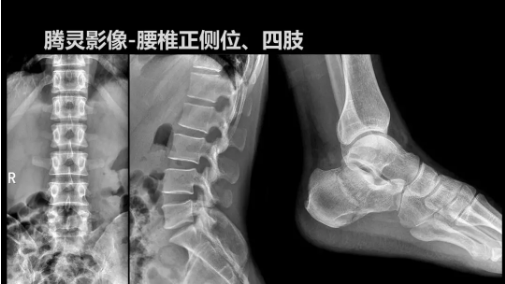

“騰靈”是安健科技的第四代動態(tài)DR產(chǎn)品,可實現(xiàn)全科室應用。如各類常規(guī)的X線檢查、消化道檢查、骨科檢查、婦科、兒科檢查等。此外,安健科技為“騰靈”在真正意義上實現(xiàn)多科室、多功能診斷進行了多項針對性設計。